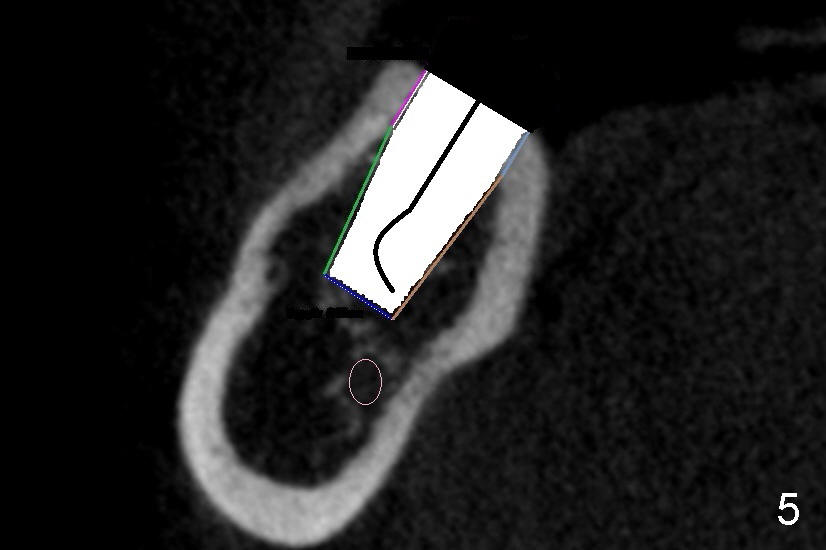

然后小钻头换大钻头,多用冷水冲洗灌注,每次控制好钻头深度,不敢越雷池一步。图四显示直径六毫米的洞(O, osteotomy),颊舌侧骨头好像都有一毫米厚。当洞钻相当大时,不妨用骨匙或者探针(图五:示意图)检查骨壁有没有穿孔,尤其是穿到神经管里(圆圈)。据说碰到神经管时,你会觉得突破感。如果手脚和脑子都很笨,你可能根本察觉不到。比较客观的迹象是出血比较明显。这时可能不要继续钻孔,选择短粗的钻头以及植牙,或者悬崖勒马,术后让病人服用激素减少水肿。